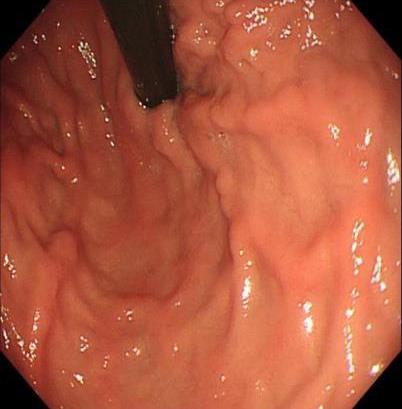

• 获得性免疫缺陷综合征合并马尔尼菲篮状菌导致肠道感染的内镜下表现(附6例报告)

2026, 32(3):84-88. DOI: 10.12235/E20250461

摘要 (32) HTML (27) PDF 3.50 M (26) 评论 (0) 收藏

摘要:目的 探讨获得性免疫缺陷综合征(AIDS)合并马尔尼菲篮状菌(TM)感染导致肠道感染的内镜下特征。方法 回顾性分析2022年11月-2024年10月于该院确诊为AIDS合并TM感染导致肠道感染的6例患者的临床资料。包括:临床症状、实验室检查、影像学检查、内镜检查和病理检查等。结果 6例患者中,男5例,女1例;发病年龄26~67岁;AIDS合并TM感染导致肠道感染患者的临床表现为:腹泻、腹痛、腹胀和恶心呕吐。其中,2例有消化道出血表现。实验室检查:6例患者外周血白细胞计数为(1.37~4.49)×109/L,血红蛋白计数为(67~99)g/L;CD4+T淋巴细胞为(1~52)个/μL,CD8+ T淋巴细胞为(61~321)个/μL,CD4+T淋巴细胞/CD8+T淋巴细胞比值为(0.01~0.18)。6例患者均行HIV RNA检测。其中,5例HIV RNA阳性。血培养:可见丝状真菌,报告显示为TM。影像学检查:6例患者CT结果可见肠系膜及腹膜后多发淋巴结肿大。内镜检查:6例患者内镜下均可见肠道病变。其中,十二指肠糜烂溃疡2例,结肠多发糜烂溃疡4例。病理检查:6例患者幽门螺杆菌(Hp)结果均为阴性,黏膜下可见成簇的小球形真菌孢子,符合TM感染;特殊染色:PAS(+),六胺银染色(+)。结论 当AIDS晚期患者出现消化道症状时,应警惕TM感染,病变部位常见于全结肠和直肠,亦可累及十二指肠,内镜下表现多为溃疡、糜烂和隆起性病变,形态表现无特异性;及时行胃肠镜检查、病理活检、特殊染色和免疫组化是确诊的关键。